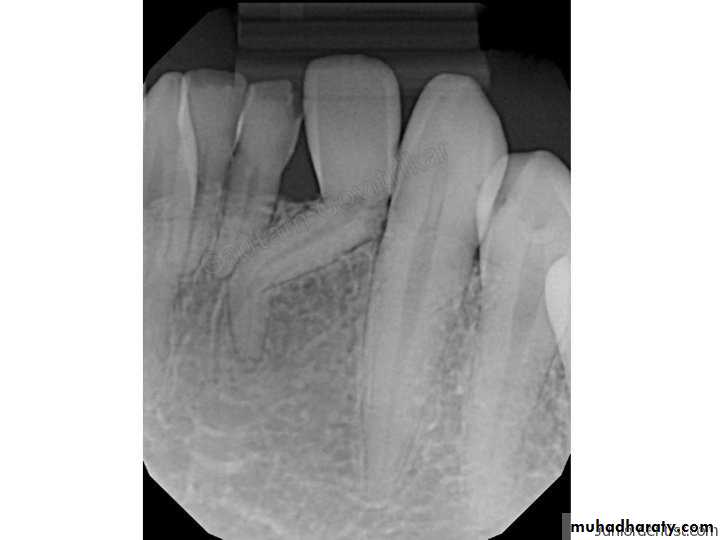

Extraction Using Labial Approach

Radiograph showing impacted maxillary canines. Right canine is located labially while left canine is located palatally

Clinical photograph of the labial area where the right canine is localized labially